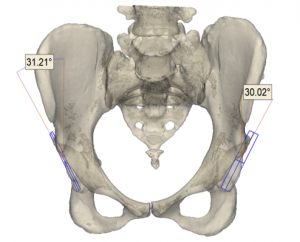

Es treballarà amb una mostra prevista de 180 pacients d’entre 18 i 80 anys dels set centres implicats, i aquests es dividiran en dos grups: un grup experimental tractat amb cirurgia digital 3D i un grup control tractat amb cirurgia convencional. Els procediments quirúrgics estudiats seran l’osteotomia de radi, una tècnica utilitzada per corregir malformacions del radi; l’artroplàstia acetabular de maluc, per tractar el desgast del maluc mitjançant la substitució dels components de l’articulació; i l’artròdesi de columna, que fusiona les vèrtebres per tractar dolor causat per fractures o malalties degeneratives.

Procés per tractar l’artroplàstia de maluc amb cirurgia digital 3D, des de la planificació digital 3D a la impressió 3D per crear un producte sanitari personalitzat.

En aquest sentit, segons afirma Fillat, la tecnologia 3D ha guanyat pes, especialment en cirurgia ortopèdica i traumatologia, perquè “permet crear models anatòmics exactes i guies quirúrgiques personalitzades a partir de les imatges del pacient, i simular digitalment el procediment quirúrgic, millorant la precisió i reduint els marges d’error”.